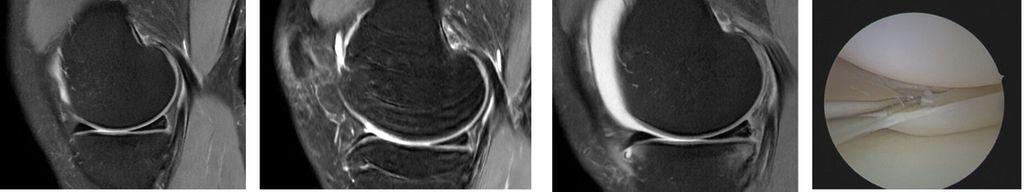

Dies verdeutlicht der Fall einer 46 Jahre alten Patientin mit atraumatischen Schmerzen im medialen Kniegelenk links (Abb. 2). In der präoperativen MRT-Diagnostik zeigt sich der degenerative Innenmeniskuswurzelriss (linkes Bild, Pfeil). In der präoperativen Röntgen-Ganzbeinaufnahme im Stehen ist ein Varus-Malalignment von 4° zu erkennen (Bilder in der Mitte). Es erfolgte eine arthroskopische Innenmeniskuswurzelrefixation mittels transtibialer Auszugsnaht, kombiniert mit einer valgisierenden medial öffnenden hohen tibialen Osteotomie (rechts).